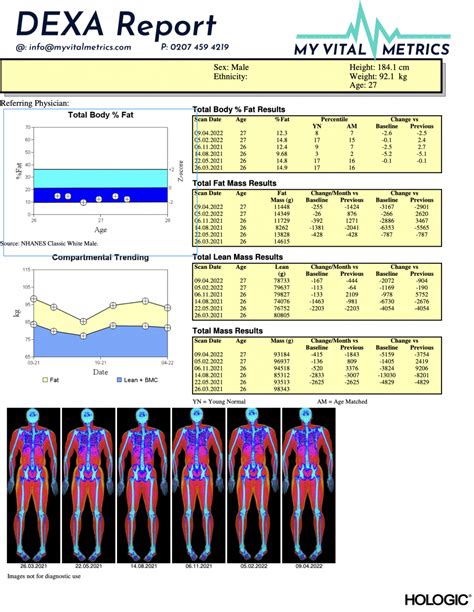

Once your scan is complete, you will receive a comprehensive report. It can be overwhelming to see all the data, but focusing on a few key metrics will help you understand your Dexa body fat results effectively. The report will typically display your total body fat percentage, which is the most common metric used to track progress.

Interpreting Progress Over Time

One of the most powerful uses of a Dexa body fat scan is longitudinal tracking. Many people fall into the trap of “weight loss” rather than “fat loss.” For example, if you start a new strength training program, you might notice your scale weight goes up or stays the same. A Dexa scan might reveal that your body fat percentage actually decreased while your lean muscle mass increased.

This "recomposition" is often missed by standard scales. By tracking your body composition every three to six months, you can adjust your caloric intake and training volume to optimize your results. If you notice your lean mass is stagnant, you might need to increase protein intake or adjust your lifting intensity. If your fat percentage isn't dropping, you may need to look closer at your daily energy expenditure.